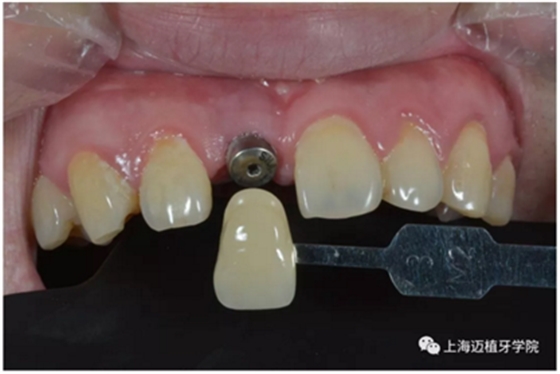

比色:3/M2

氧化鋯個(gè)性基臺(tái)